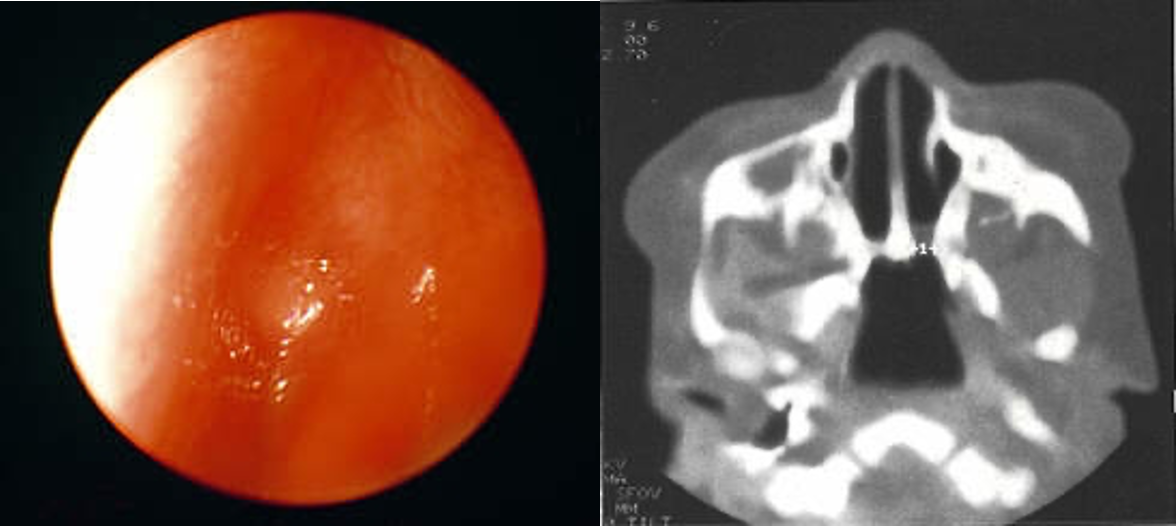

Choanal Atresia

- Due to persistence of the primitive bucconasal membrane

- Unilateral or bilateral

- Bony, membranous or mixed

Unilateral Choanal Atresia

- Usually diagnosed late in life

- Presents by unilateral nasal obstruction and unilateral mucoid nasal discharge

Diagnosis

- Clinical examination: “mirror test”

- Inability to pass a catheter into the nasopharynx

- Endoscopy

- Radiographs